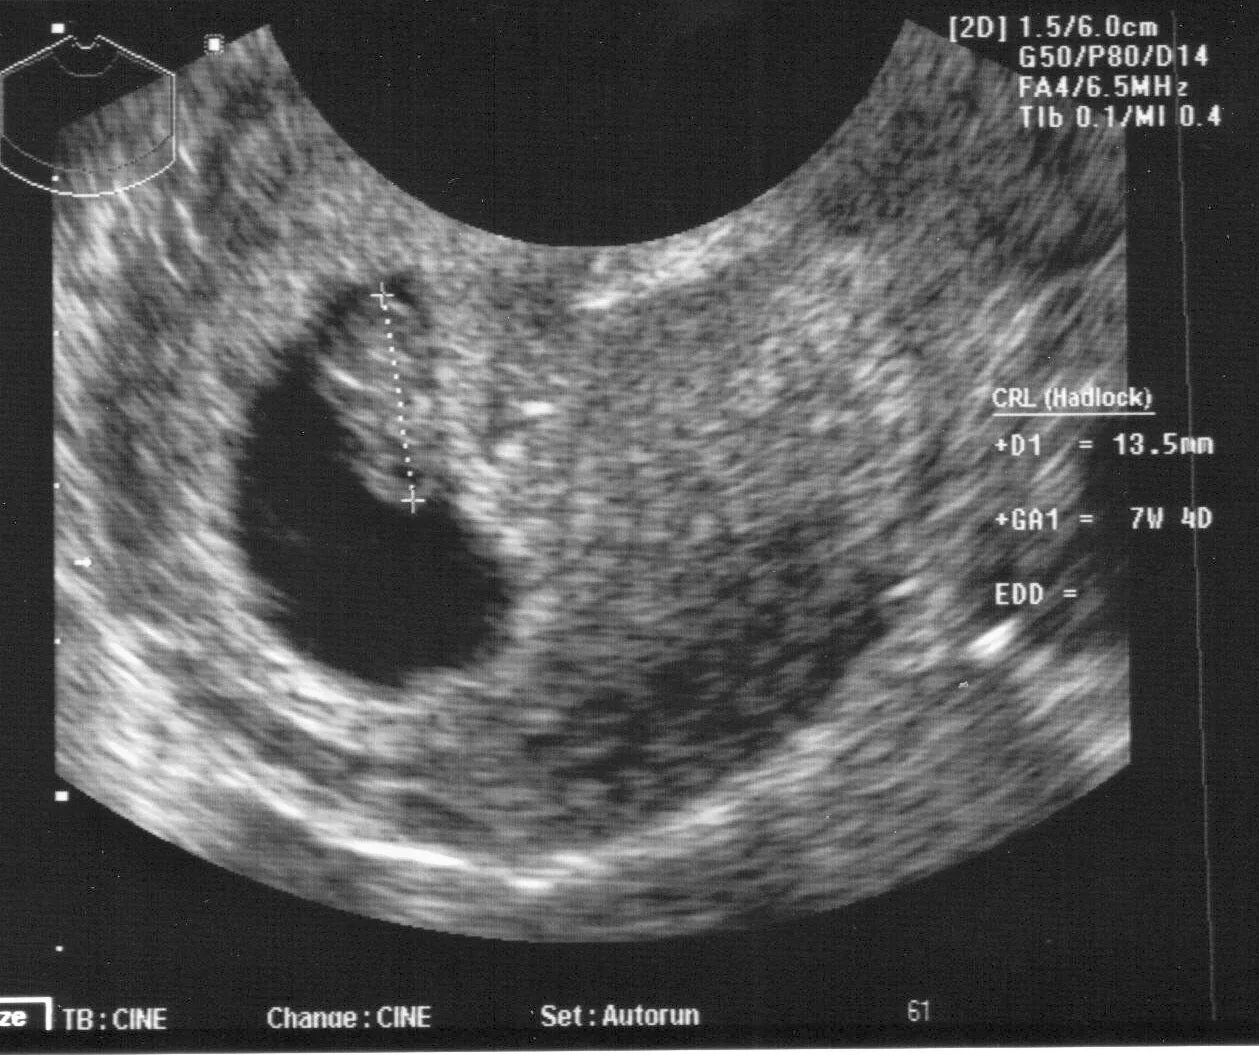

7 недель какой ребенок